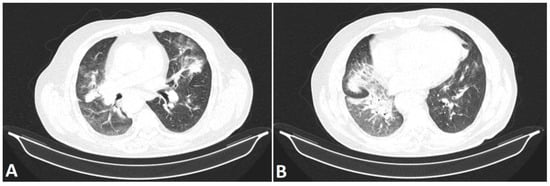

- Mostafavi, S.M. COVID19-CT-Dataset: An Open-Access Chest CT Image Repository of 1000+ Patients with Confirmed COVID-19 Diagnosis 2021. Available online: https://doi.org/10.7910/DVN/6ACUZJ (accessed on 21 June 2022).

- Yan, T. COVID-19 and Common Pneumonia Chest CT Dataset (416 COVID-19 Positive CT Scans). 2020, Volume 2. Available online: https://doi.org/10.17632/3y55vgckg6.2 (accessed on 21 June 2022).

- Yan, T. COVID-19 and Common Pneumonia Chest CT Dataset (412 Common Pneumonia CT Scans). 2020, Volume 1. Available online: https://doi.org/10.17632/ygvgkdbmvt.1 (accessed on 21 June 2022).

- Li, P.; Wang, S.; Li, T.; Lu, J.; HuangFu, Y.; Wang, D. A Large-Scale CT and PET/CT Dataset for Lung Cancer Diagnosis 2020. Available online: https://doi.org/10.7937/TCIA.2020.NNC2-0461 (accessed on 21 June 2022).